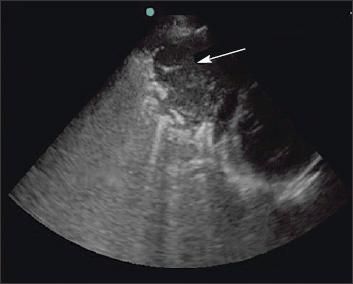

The border between atelectatic and aerated lung is often visible, and progressive expansion of aerated lung can be observed during thoracentesis. Ultrasonography may reveal lung tumors or pleural nodules and masses and can easily distinguish these from a coexisting pleural effusion (Figure 2).2-4

Figure 2 –

A pleuralbased left lung mass can be seen on this ultrasonogram (arrow). Ultrasonography can easily distinguish tumors from coexisting pleural effusion.